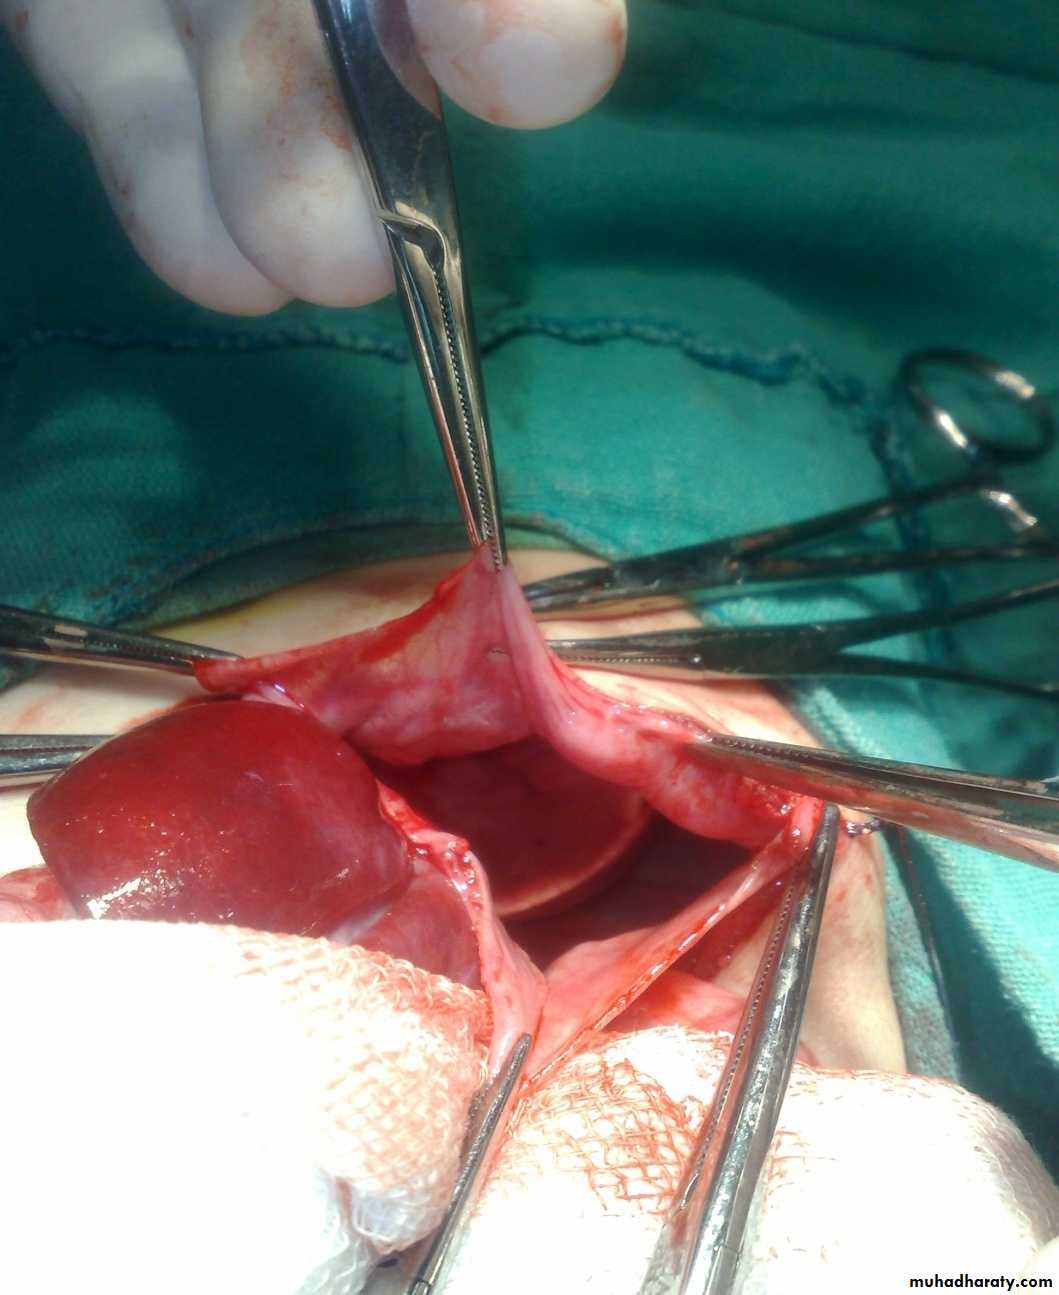

Defect=sac